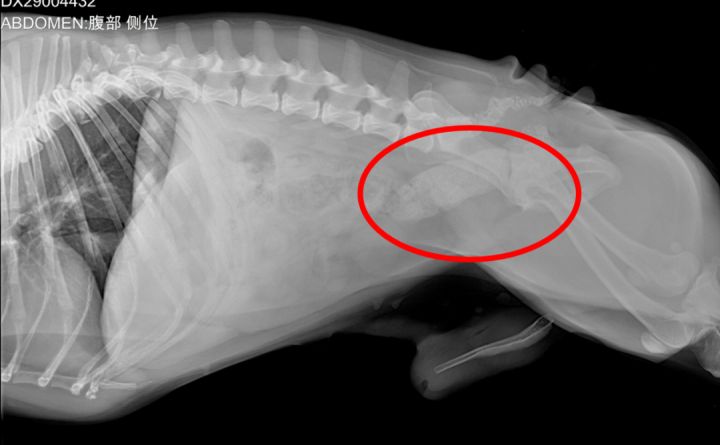

日常生活中,比较常见的就是由于饮食不当导致便秘,比如吃了纸、头发、骨头等。下面就是我家法斗弟弟的X光片 - 便便都堵在结肠和直肠了。

如果发现狗狗便秘症状强烈,并且时间较长,就一定要去医院就诊。正常诊断便秘的方法就是通过X光片、腹部超声以及医生触摸。确诊之后再治疗,是最安全的方法。